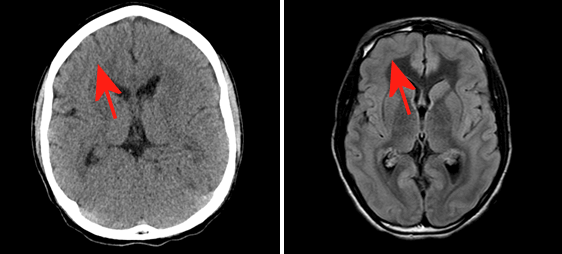

Diagnosis: Band Heterotopia

Figure 1: A: Axial non contrast head CT demonstrates a rind of subcortical tissue isodense to cortex (red arrow). B: Axial FLAIR MRI demonstrates a band of signal similar to cortex throughout the subcortical white matter (red arrow).

Band heterotopia is one form of heterotopia where the abnormal grey matter ribbons the subcotical space giving the appearance of a duplicated cortical layer. Children most commonly present with developmental delay and / or seizures. Treatment is symptomatic and may include antiepileptics or surgical resection for intractable partial seizures.